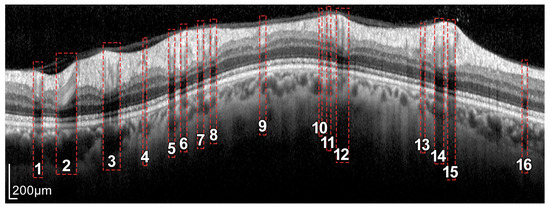

In addition, because blood vessels are located just above the retina, a shadowing effect appears on the retinal layers. As observed in Figure 5, these vessels cross the circumference of analysis perpendicularly, casting a shadow on the retinal layers at these crossing points. This results in intensity inhomogeneities, boundary artifacts, and darkened areas in the layers to be segmented, as portrayed in Figure 6. This further complicates the segmentation of the RNFL and hence the calculation of its thickness.

Figure 5.

Retinal fundus imaging of the eye under analysis. The green circumference represents the OCT analysis circumference centered on the optic nerve, marked with a +. The numbers represent the vessels crossing this analysis circumference.

Figure 6.

Intensity inhomogeneities and boundary artifacts caused by shadows cast by blood vessels. The numbers identify each of the vessels crossing the circular ray tracing depicted in Figure 5.